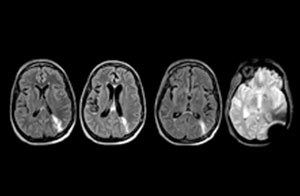

Klinische Fallbeispiele